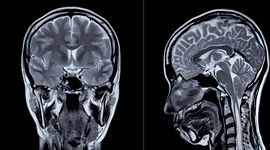

Care sunt efectele nefaste ale zborului spațial asupra creierului? Călătoria în spațiu este dură pentru organismul uman, iar un nou studiu arată că, după o misiune spațială, creierul se deplasează în sus și înapoi și se deformează în interiorul craniului.

Obiectivul oamenilor de știință a fost să analizeze mai detaliat aceste schimbări. Aceștia au examinat imagini RMN ale creierului de la 26 de astronauți care au petrecut diferite perioade în spațiu, de la câteva săptămâni la peste un an. Pentru a urmări mișcarea creierului, cercetătorii au aliniat structura craniului în scanările realizate înainte și după misiuni.

Această comparație le-a permis să măsoare modul în care creierul s-a deplasat în raport cu craniul. În loc să trateze creierul ca pe un singur bloc, l-au împărțit în peste 100 de regiuni și au urmărit deplasarea fiecăreia. Astfel, au identificat tipare care nu erau vizibile în analizele globale.